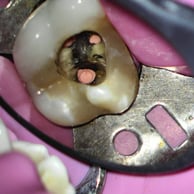

CASOS CLÍNICOS

Abaixo você encontra fotos de alguns dos tratamentos realizados.